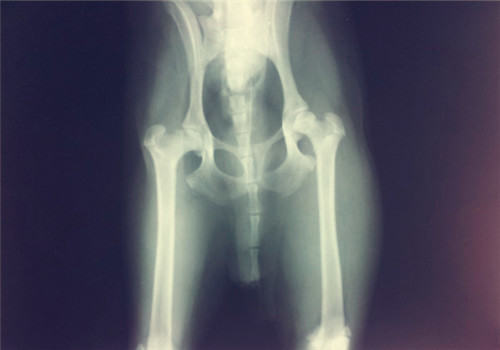

3、骨关节病:

由于肥胖而导致的体重高于正常,这会导致对骨关节的负担加重,使得一些骨关节病的

发病率会增加。这多表现在大型犬,当大型犬的幼犬在幼年时因能量摄入过多而导致肥胖后,会引发多种骨科疾病或加重髋关节发育不良的情况。同时,由于骨关节问题而导致的动物运动减少,导致能量消耗减少,而能量的摄入不便,会进一步加重肥胖,形成恶性循环。

髋关节发育不良